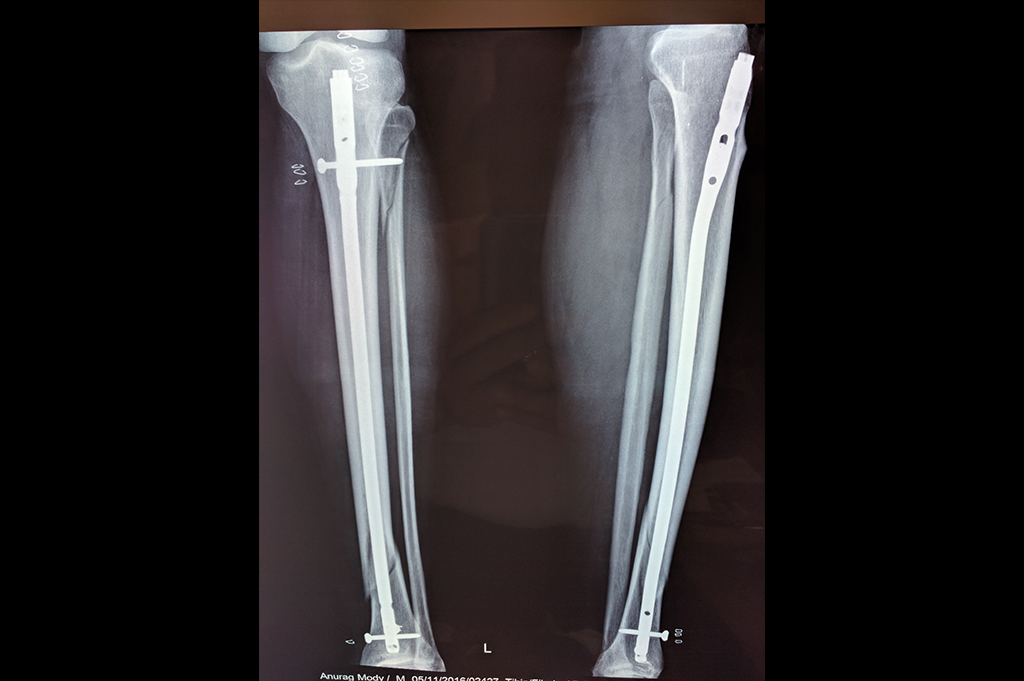

Tibia Nailing